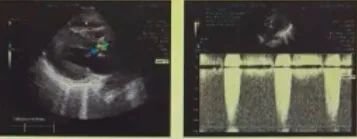

心脏彩超

峰值流速:5.3M/s;

最高跨瓣压差;118mmHg;

平均跨瓣压差:61mmHg;

左室射血分数EF值: 0.62;

左室舒张末期内径(LVD):41mm;

主动脉瓣评估:主动脉瓣中重度狭窄并轻度反流,二尖瓣反流、三尖瓣反流,心包积液。